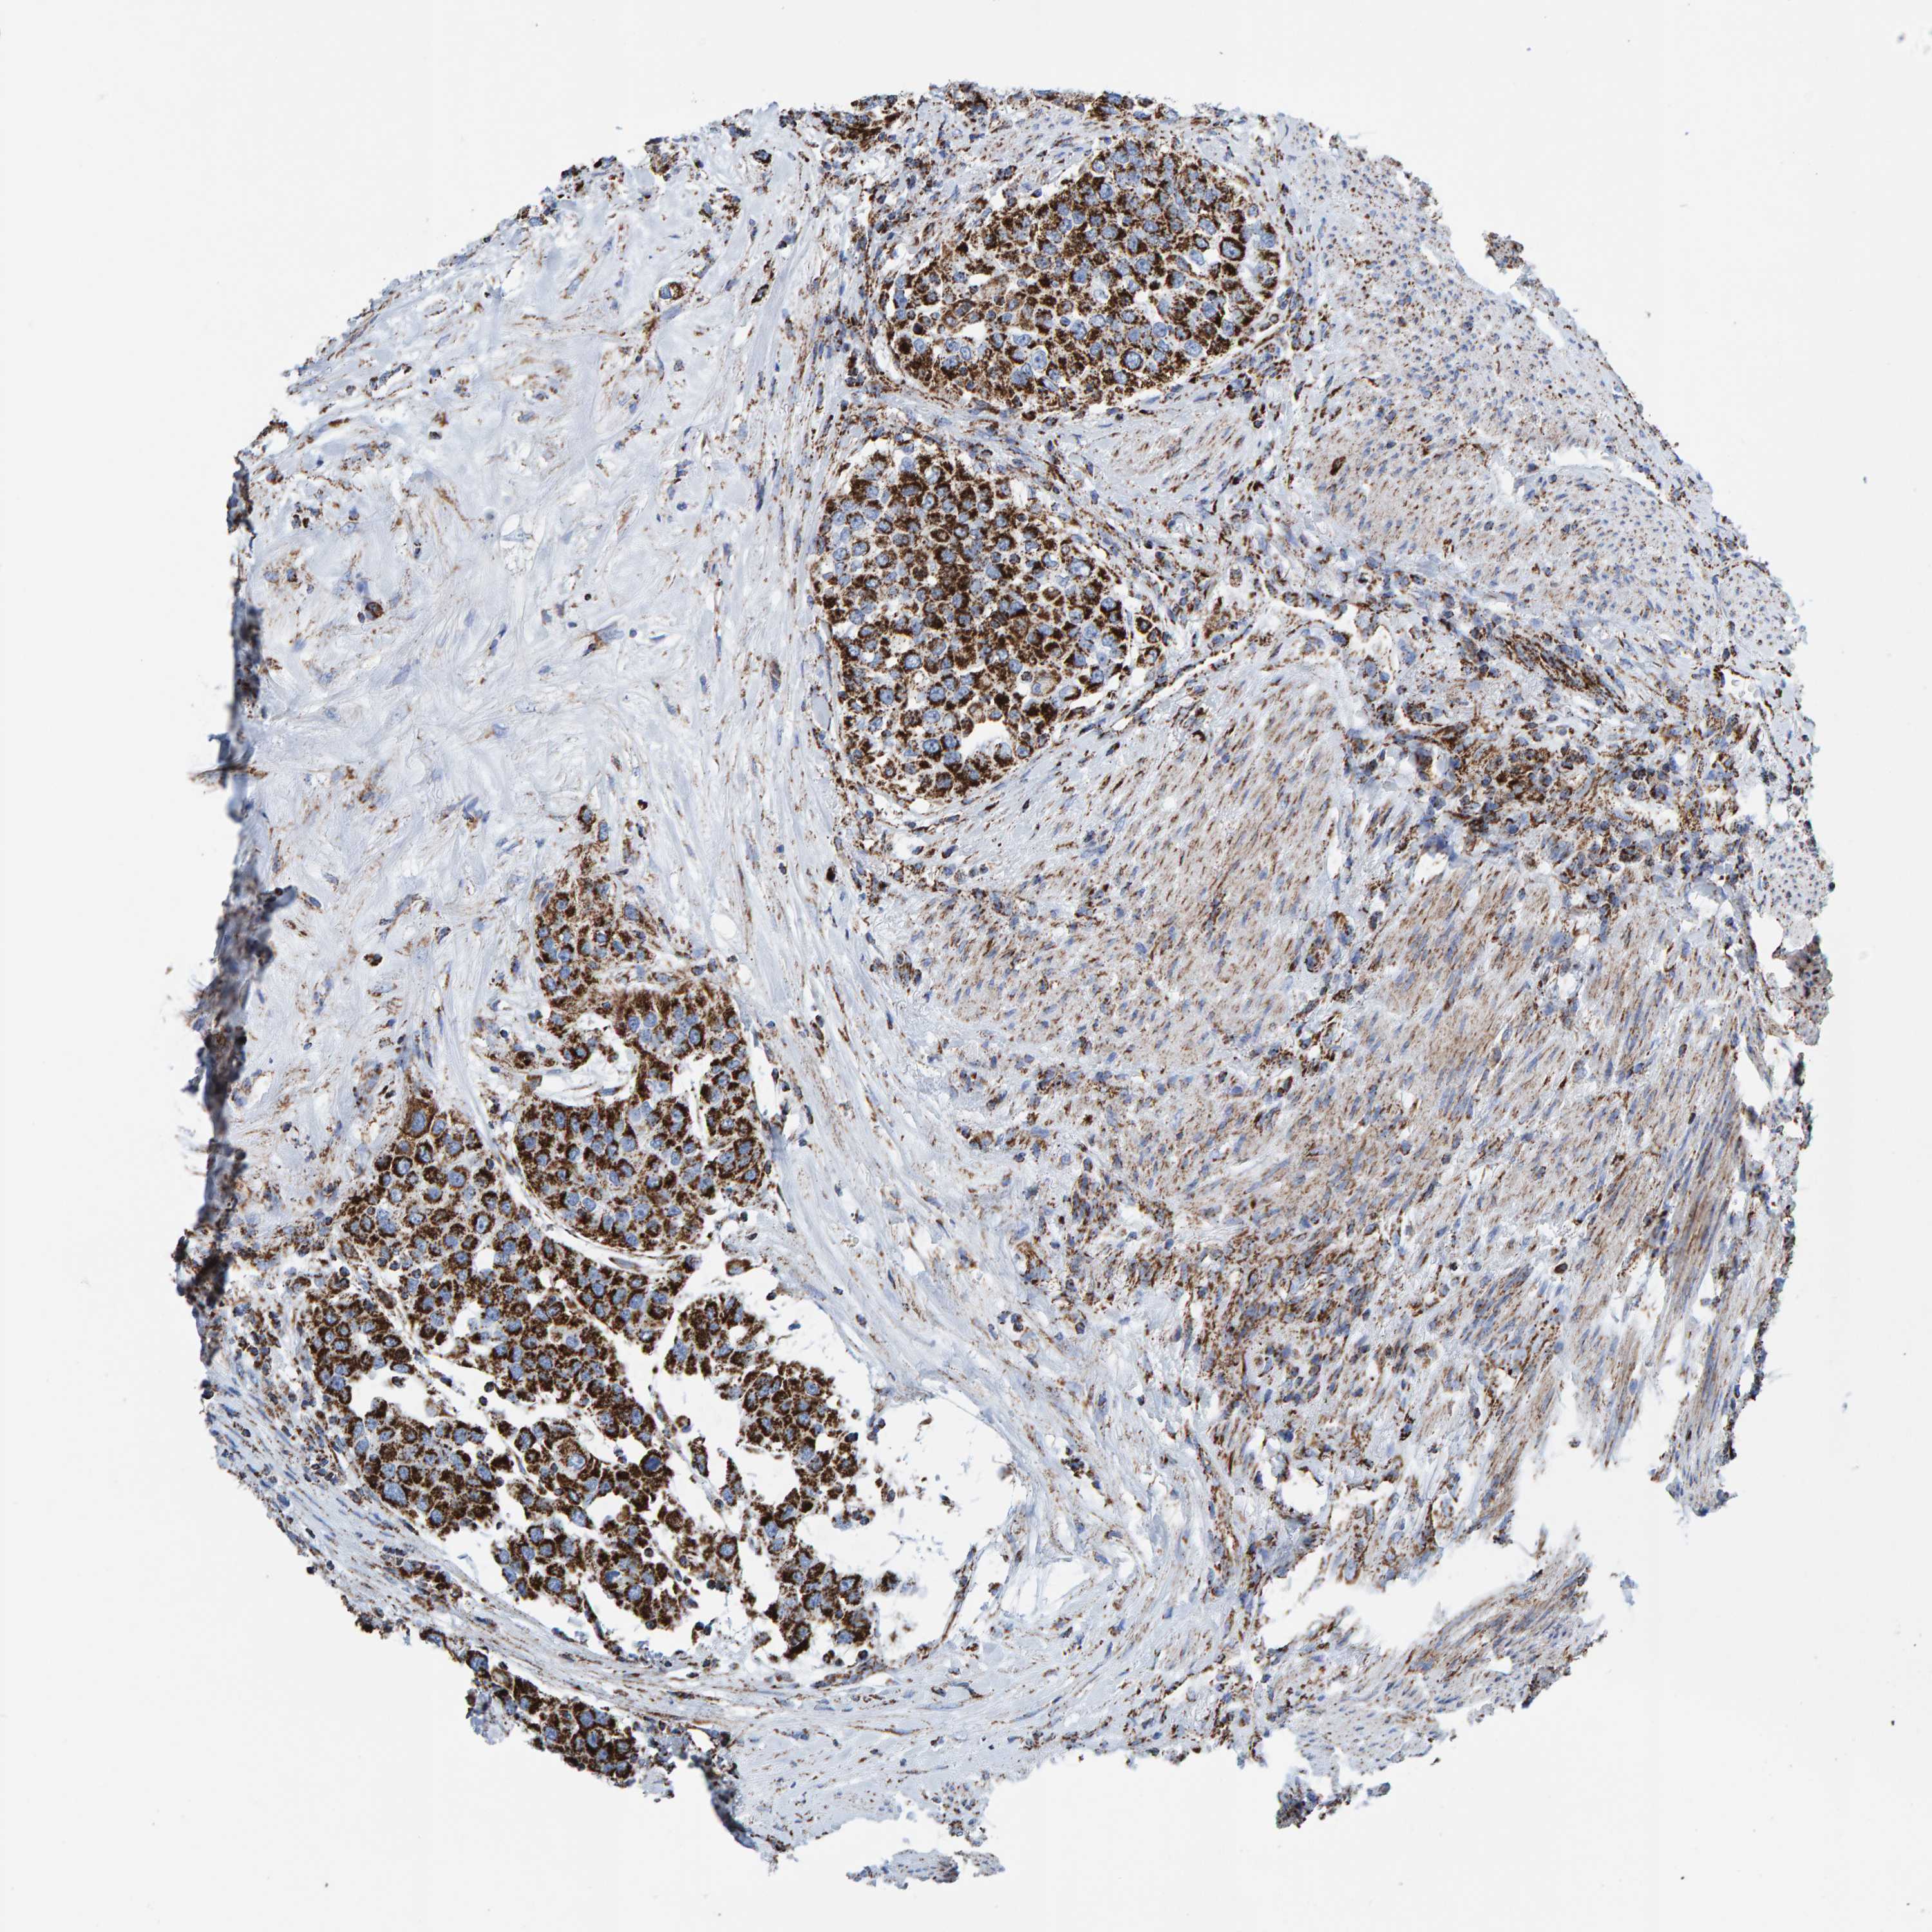

UROTHELIAL CANCER - Protein expressioni

A mouse-over function shows sample information and annotation data. Click on an image to view it in a full screen mode. Samples can be filtered based on level of antibody staining by selecting one or several of the following categories: high, medium, low and not detected. The assay and annotation is described here.

Note that samples used for immunohistochemistry by the Human Protein Atlas do not correspond to samples in the TCGA dataset.

Antibody stainingi

Antibody staining in the annotated cell types in the current human tissue is reported as not detected, low, medium, or high, based on conventional immunohistochemistry profiling in selected tissues. This score is based on the combination of the staining intensity and fraction of stained cells.

Each image is clickable and will lead to virtual microscopy that enables deeper exploration of all samples and also displays staining intensity scores, fraction scores and subcellular localization as well as patient and tissue information for each sample.

Antibody HPA022853

Antibody HPA023043

Antibody HPA023048

Staining

High

Medium

Low

Not detected

Intensity

Strong

Moderate

Weak

Negative

Quantity

>75%

75%-25%

<25%

None

Location

Nuclear

Cytoplasmic/membranous

Cytoplasmic/membranous,nuclear

Urothelial carcinoma, Low grade

Urothelial carcinoma, High grade